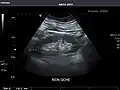

Right kidney -

Kidneys: Right and left kidneys measure 11.5 cm and 12 cm in length respectively. No hydronephrosis. Small left lower pole kidney cyst.